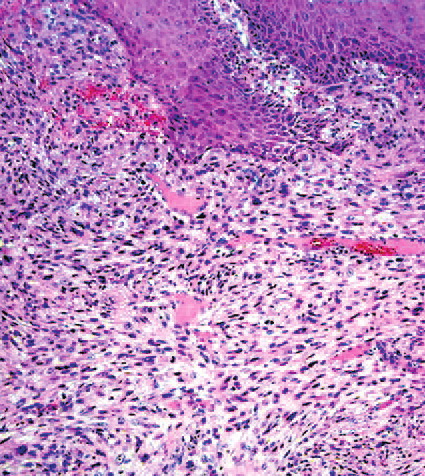

fibroxanthoma = الورم الاصفر الليفي